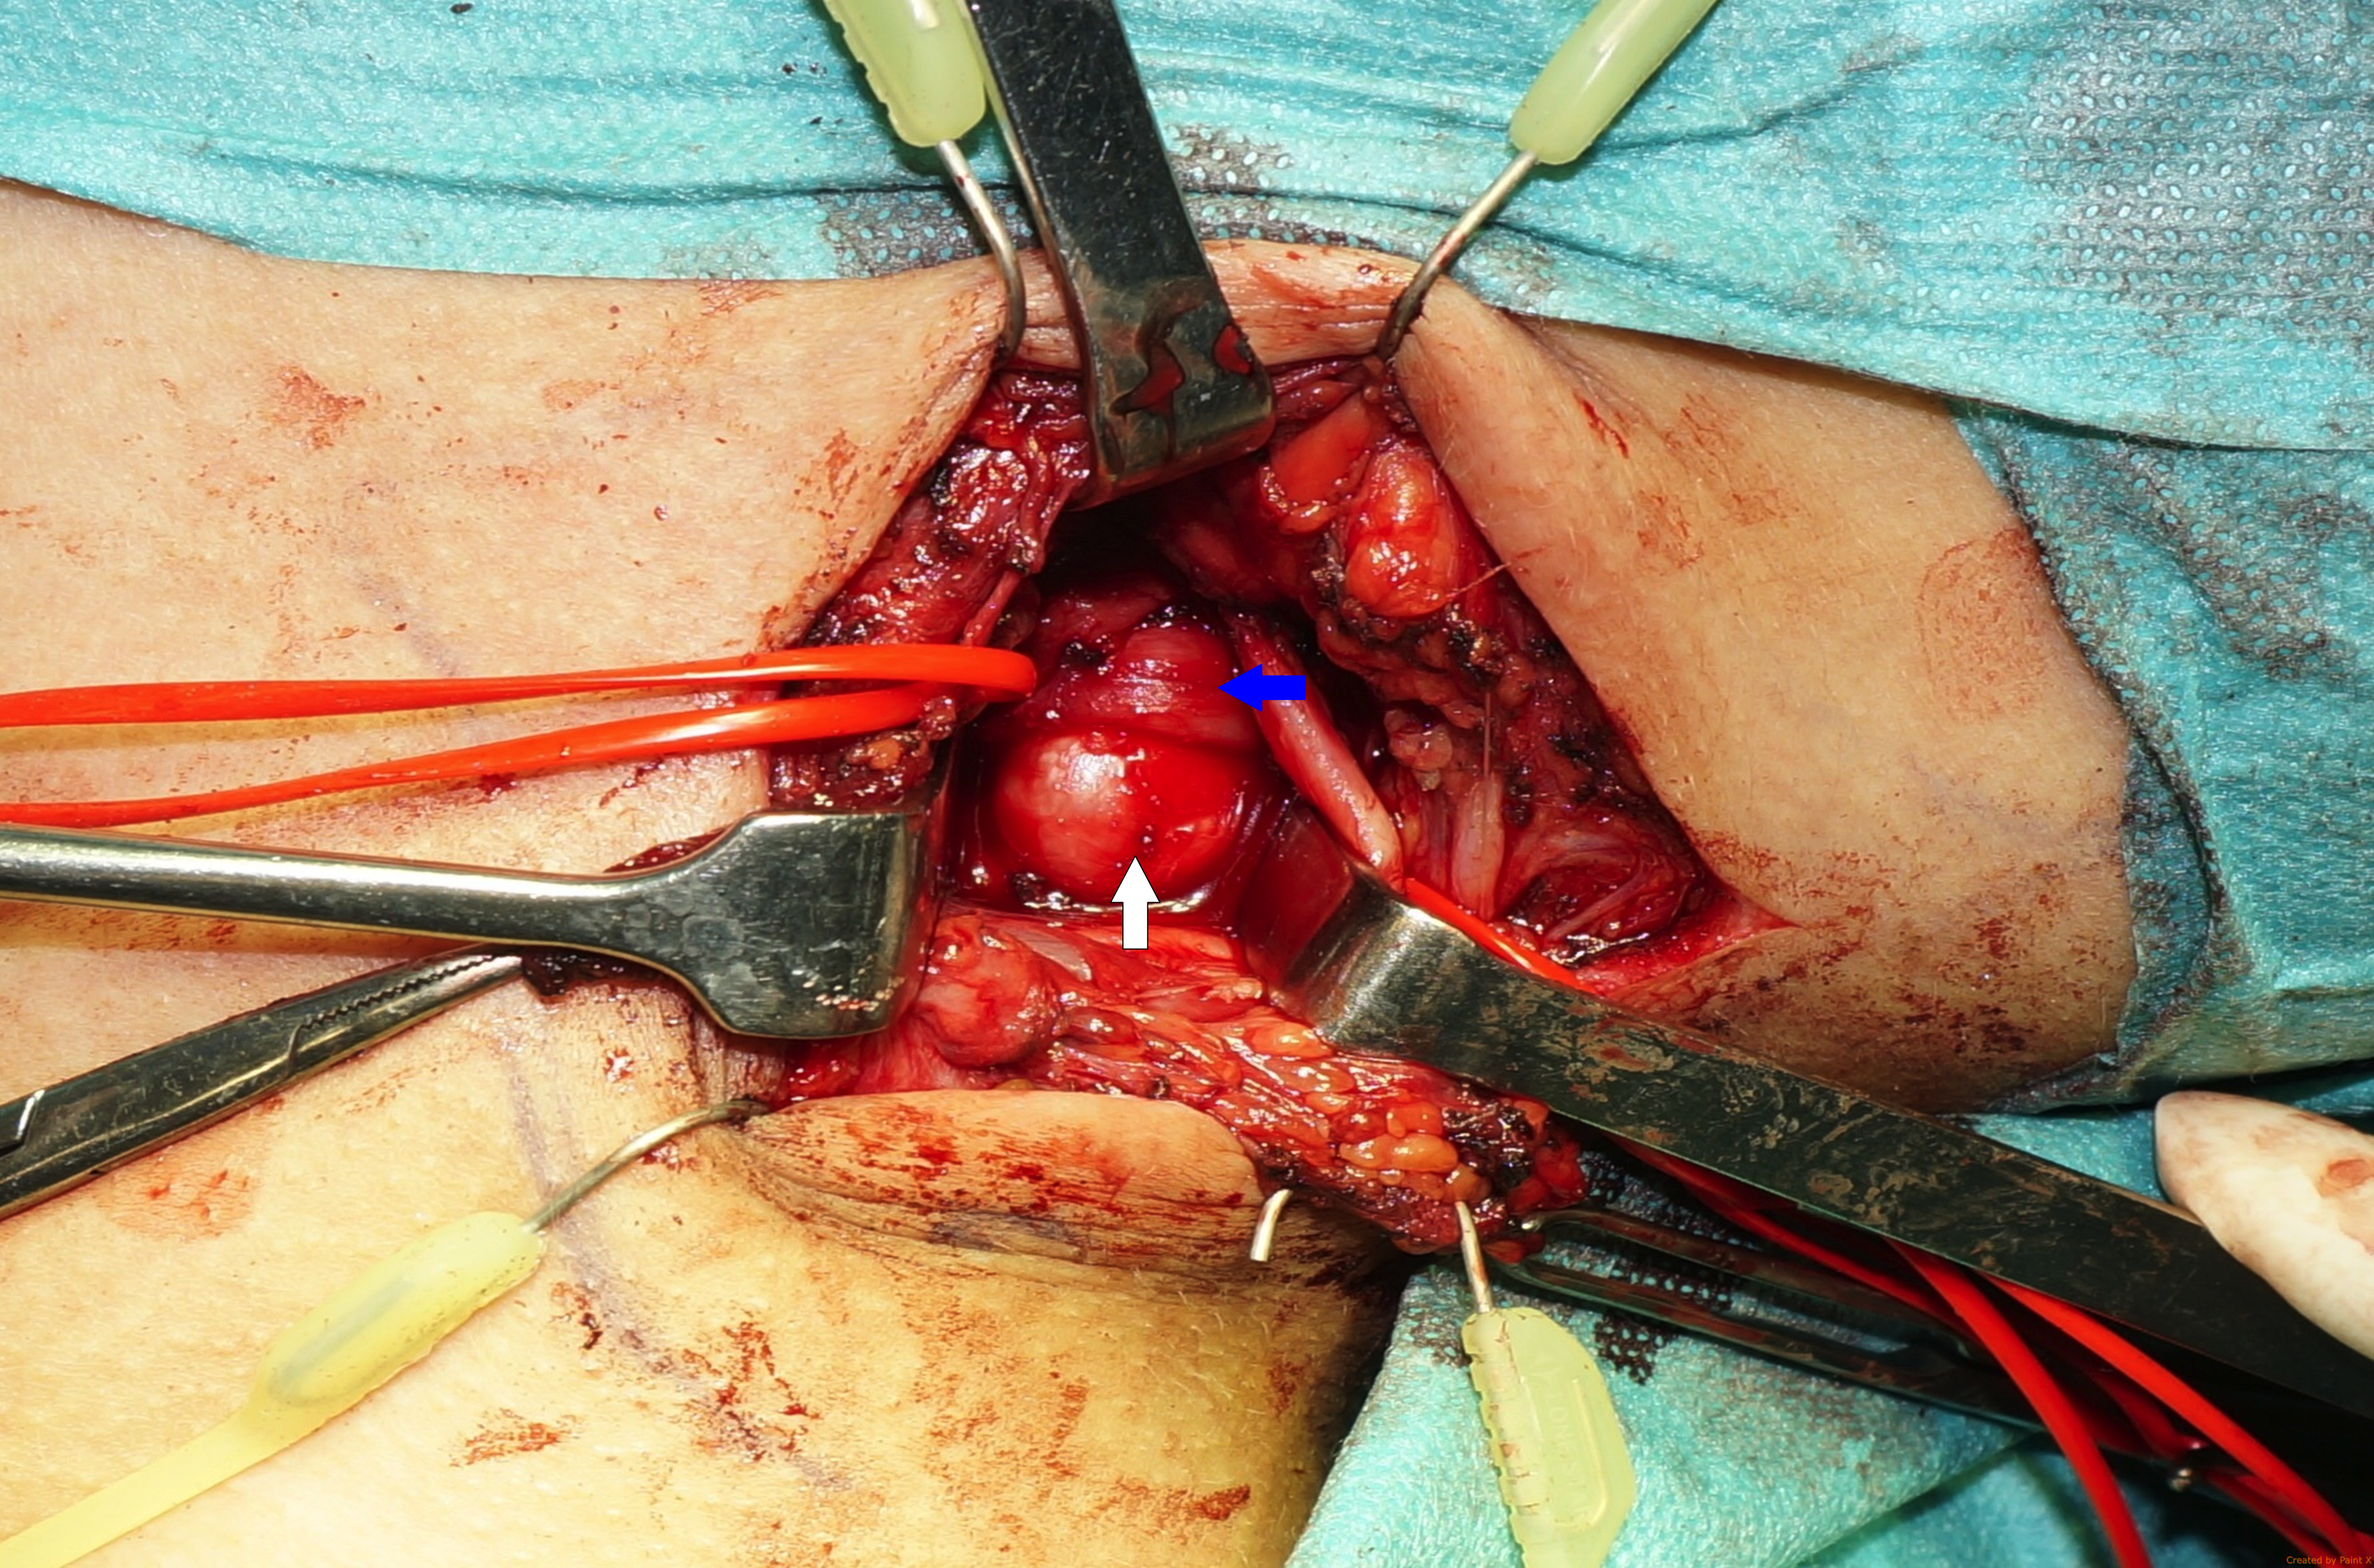

Next, the anterior and middle scalene muscles were divided from the first rib. The 3 trunks of the brachial plexus were visualized and gently protected. A supernumerary anomalous rib with a 90-degree curvature was unveiled, which was articulated to the first costal arch. Compression of the inferior trunk of the brachial plexus and the subclavian artery was obvious (Figure 4). The first rib was encircled and divided (Figure 5). It was decided not to remove the posterior edge of the first rib because of the iatrogenic risk of C8 root damage. The SCM muscle was repaired, and the wound was closed in a subcuticular fashion over a suction drain. The postoperative period was uneventful, and the patient was discharged home on the third day postoperative.

Figure 4. The supernumerary anomalous rib with a 90-degree curvature articulated to the first costal arch. A compression of the inferior trunk of the brachial plexus is evident. White arrow: anomalous rib; blue arrow: inferior trunk.